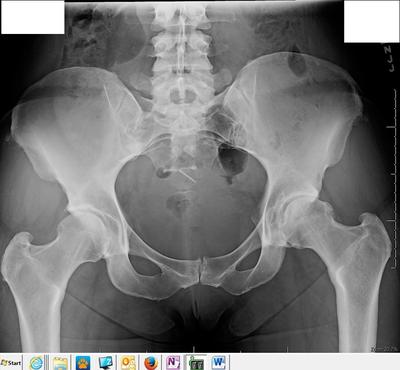

Hip xrays 6 weeks apart different facilities

Pain started June 5th, 2016 while running, thought stress fracture, had two xrays 6 weeks apart, both state mild hip arthritis. Had MRI, still mild hip arthritis. PT said "frozen hip" was some of my issue, that is better after 8 weeks of working the hip, still cannot run, pain begins soon after running. To me on the xray's it looks like my pelvis is out of alignment. Left side is higher than right side and I feel my left leg is shorter. Wonder if my pain is due to hips not being in alignment?

This is interesting! And thought provoking. Yes, you do have some mild arthritis but that's been slowly developing over the years. What is unusual is the very large CAM deformity arrowed; you have a condition called femoro acetabular impingement syndrome. It causes the frozen hip that your PT describes, and isn't new either; you may not have realised it but you've had a stiff hip for years.

Yes, there is some distorsion of the pelvis; was this radiograph taken standing? If so you have a short leg and, combined with the CAM deformity is why it's turning arthritic. You should be wearing an orthotic in your shoe, thicker on the right.

What I can't tell is where your pain is, and whether the sacroiliac joint is involved; it's likely to be, and treating that, together with gentle daily exercises of your hip is what is likely to save the day.